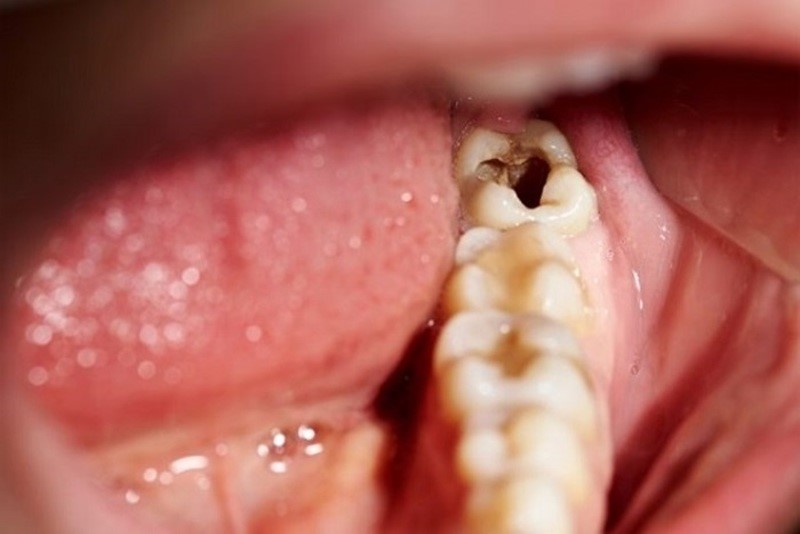

Các bệnh lý như sâu răng, viêm tủy, viêm quanh chóp răng hoặc viêm nha chu nếu không được điều trị kịp thời sẽ khiến vi khuẩn xâm nhập vào ống tủy, gây viêm nhiễm kéo dài. Tủy răng dần mất khả năng phục hồi và dẫn đến hoại tử.

Các thủ thuật nha khoa như trám răng, bọc sứ, điều trị tủy, làm cầu răng nếu thực hiện sai kỹ thuật có thể dẫn đến tổn thương tủy hoặc tạo điều kiện cho vi khuẩn xâm nhập. Tình trạng này khiến tủy viêm âm thầm và biến chứng làm chết tủy răng.

(Trám răng sai kĩ thuật làm miếng trám dễ bị mẻ, bung tạo điều kiện cho vi khuấn thâm nhập vào tủy răng)(**)